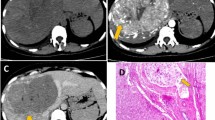

Peritumoral enhancement is defined as the existence of a detectable, arterial-enhancing portion adjacent to, but separate from, the tumor border, as identified on arterial phase images, which later became isointense with the background liver parenchyma in the delayed phase [9]. Further, peritumoral hypointensity on HBP is defined as an irregular, wedge-shaped, or flame-like hypointense area of liver parenchyma located outside of the tumor margin [10]. Their association with MVI has been controversially reported [9, 11,12,13,14,15,16,17]. Hence, we conducted an analysis of the available evidence to reach a more conclusive result considering the relationship between peritumoral imaging features and MVI.

The summary result revealed a significant association between peritumoral enhancement and MVI, with an OR 4.04 [2.23, 7.32], and p < 0.05 (Fig. 2). The inconsistency index I2 was 45.4%, indicating moderate heterogeneity. Meta-regression indicated a possible source of bias in the origin of study (p < 0.05), the imaging test applied (p < 0.05), and the tumor number included (p = 0.02). Subgroup analysis revealed statistically significant results in the group from Korea (OR 7.60 [4.39, 13.17]) and China (OR 2.09 [1.12, 3.92]), and in the solitary (OR 4.32 [1.93, 9.66]) and multiple (OR 3.45 [1.21, 9.78]) tumor groups. When stratified by imaging test, the result of the studies using MRI was statistically significant (OR 4.98 [2.76, 8.99]), but was not significant for those using CT (OR 2.01 [0.62, 6.52]) (Table 2). Sensitivity analysis and Egger’s test showed no small-study effects (p = 0.58). We attempted to apply peritumoral enhancement as the only diagnostic criteria for MVI, which yielded a sensitivity of 0.29 and specificity of 0.90 (Fig. 3). The peritumoral hypointensity on HBP was also significantly associated with MVI, with an OR = 10.62 [5.31, 21.26], and p < 0.05 (Fig. 4). The heterogeneity was low (I2 = 0). A diagnostic analysis revealed similar results with low sensitivity (0.40) and high specificity (0.94) (Fig. 5).

Our meta-analysis indicated significant association between peritumoral imaging features and MVI, but poor diagnostic accuracy. In clinical practice, when MVI is indicated preoperatively, the diagnostic accuracy can be improved with intentional expanded sampling. Adjuvant treatments such as sorafenib [27, 28] or trans-catheter arterial chemoembolization (TACE) [29] can be applied, as these approaches have been reported to improve the survival of HCC patients with MVI. Imaging method has been promising to assess MVI preoperatively, given the discovery of associations between imaging features and proteomics characteristics and gene signatures, and further association with a pathologically diagnosed MVI [30,31,32,33]. Kusano et al. [34] discovered a high level of expression of placental growth factor (PlGF) and vascular endothelial growth factor receptor (VEGFR-1) in adjacent noncancerous tissue associated with MVI. This elevated expression may induce peritumoral pathologic angiogenesis and potentiate vascular invasion [35]. Peritumoral enhancement may represent compensatory arterial hyperperfusion, after changes in hemodynamic perfusion with obstruction of the peritumoral microvessels by tumor thrombi [36]. Peritumoral hypointensity on HBP reflects decreased peritumoral uptake of the contrast agent on MRI. Nishie [37] suggested that this finding may be caused by Kupffer cells and hepatocyte injury in tumorous AP shunts in which the associated portal branches are obstructed.